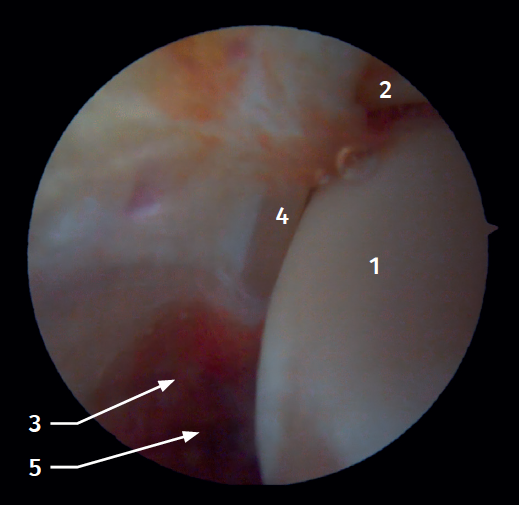

Arthroscopic anatomy of the medial complex

Arthroscopy allows us to see the deep fibers of the deltoid ligament, corresponding to the intra-articular portion of the ligament. Medial and proximal to the tip of the malleolus we have the insertion of the deep layer of the deltoid ligament. If there is no injury, we will see the anterior portion of the deep tibiotalar fibers. When injury is present, we can visualize the intermediate and posterior portion. The superficial bands, due to their more external location, are not visible by arthroscopy, unless there is no lesion of the deep bands (Figure 5).